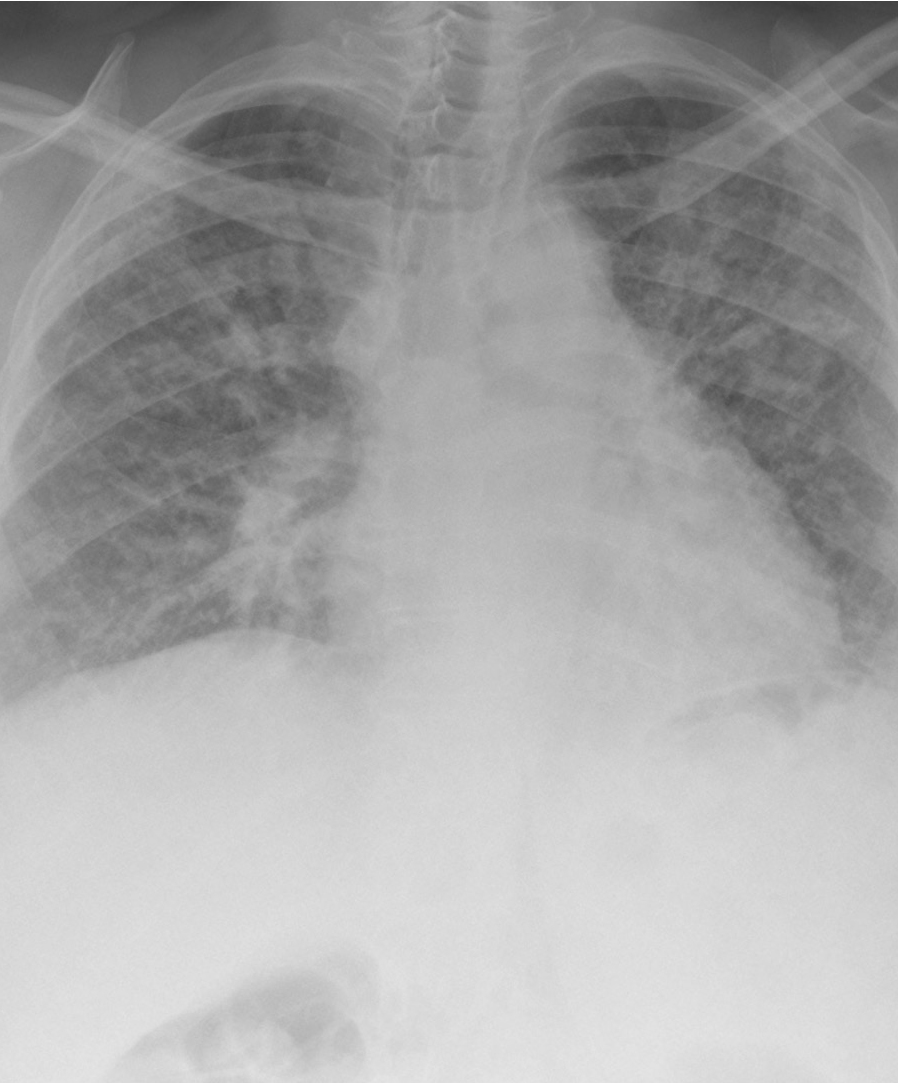

Severe pulmonary fibrosis

Severe pulmonary fibrosis(click to enlarge)

A chest X-ray is usually non-specific and cannot accurately diagnose IPF, particularly in the early stages of disease. A high resolution computed tomography (HRCT) thoracic scan is warranted to categorise the underlying lung aetiology. Honeycombing, a diagnostic and distinctive fibrosis pattern on HRCT that shows sub-plural basal-predominant reticular abnormalities, is indicative of advanced IPF. This pattern can be difficult to accurately identify even for experienced radiologists.